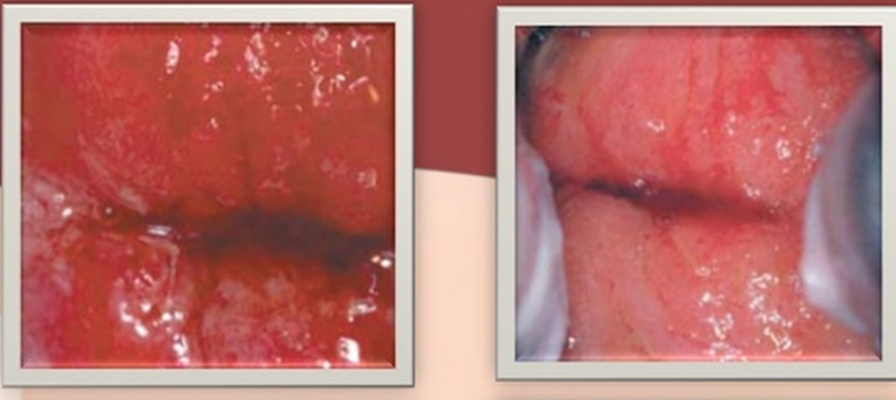

淋病圖片

淋病的症狀 (7)

淋病的症狀 (8)

淋病的症狀 (9)

淋病的症狀 (47)

淋病的症狀 (48)

淋病的症狀 (49)

淋病的症狀 (5)

淋病的症狀 (50)

淋病的症狀 (51)

淋病的症狀 (52)

淋病的症狀 (53)

淋病的症狀 (54)

淋病的症狀 (55)

淋病的症狀 (56)

淋病的症狀 (6)

淋病的症狀 (40)

淋病的症狀 (41)

淋病的症狀 (42)

淋病的症狀 (43)

淋病的症狀 (44)